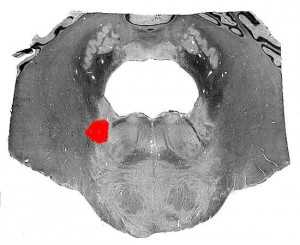

Рис. 2. Схема поражения спинного мозга при синдроме Броун-Секара (пораженный сегмент заштрихован): 1 — задний корешок; 2 — передний корешок; 3 — боковой пирамидный путь; 4 — пути задних столбов; 5 — спино-таламический путь.

Клинические симптомы Б.-С. с. обусловлены распределением афферентных и эфферентных путей в спинном мозге (рис. 2). Пирамидный путь перекрещивается на границе продолговатого и спинного мозга, волокна задних канатиков (мышечносуставная чувствительность, сложные виды поверхностной чувствительности) перекрещиваются в продолговатом мозге, чем объясняется гомолатеральная очагу симптоматика. Вегетативные нарушения на стороне очага объясняются поражением вегетативно-эффекторных путей, проходящих в спинном мозге в непосредственной близости от пирамидных путей. Спино-таламический путь, несущий в основном болевую, температурную, частично тактильную чувствительность, перекрещивается в спинном мозге в передней комиссуре, чем объясняется контрлатеральная патологическому очагу симптоматика. Зоны сегментарных нарушений чувствительности связаны с поражением сегментов спинного мозга.